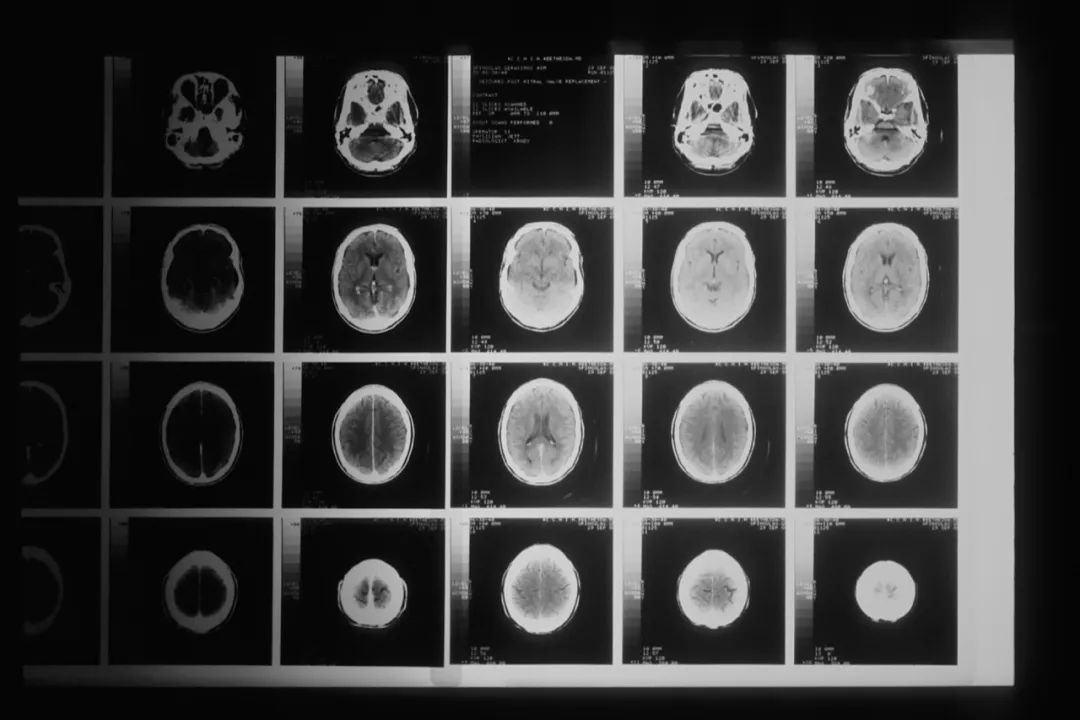

腦膠質瘤是指起源於腦神經膠質細胞的腫瘤,是成年人最常見的原發性顱內腫瘤。我國腦膠質瘤年發病率為每10 萬人中有5~8例,5 年病死率在全身腫瘤中僅次於胰腺癌和肺癌。但腦膠質瘤發病的內在機制尚不明瞭,目前確定的兩個危險因素是:暴露於高劑量電離輻射和與罕見綜合徵相關的高外顯率基因遺傳突變。

腦膠質瘤的標準療法以手術切除為主,結合放射治療與使用化學藥物替莫唑胺(TMZ)進行綜合治療。手術可以緩解臨牀症狀,延長生存期,但往往只可延長患者約三個月的壽命,因為幾乎所有患者都會面對腦膠質瘤復發的問題。醫學界當前仍未釐清這套標準療法為什麼會促使腦膠質瘤惡化。

圖源:National Cancer Institute